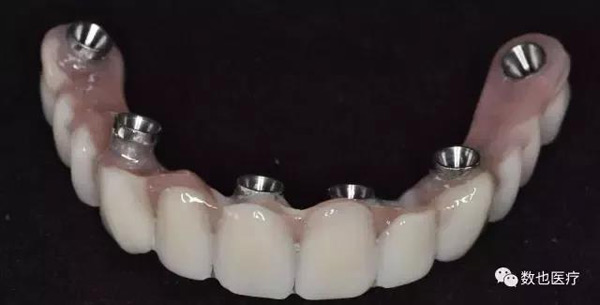

临时修复体的制作

制作完成的临时修复体